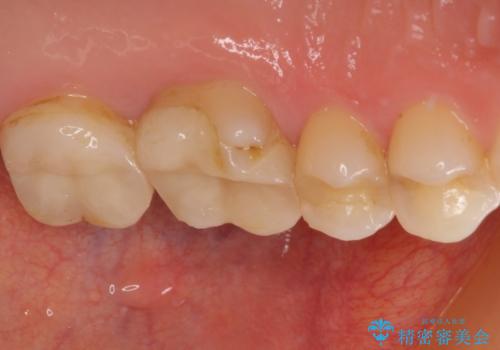

- 奥歯がズキズキと痛み、食事で噛むことができないとのことで来院された患者様です。

以前治療を受けたとき、むし歯が大きかったため、神経組織が炎症を起こす可能性があると指摘をされていたとのことでした。

レントゲン写真から、神経組織近くにまで大きな修復物が認められました。

叩いたり、冷熱や電気刺激にによるテストを行ったりとしましたが、炎症の状態は芳しくなく、根管治療を行う前提で処置を行うこととしました。